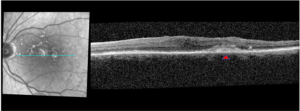

At this visit, the patient was diagnosed with a tractional ERM complicated by broad VMT and anomalous PVD OS. After consulting with a retina specialist about the retinal changes, observation was recommended. The patient missed his 1-month follow-up but presented 6 months later. At this visit, his VAs were stable and retinoschisis had decreased in size, but central macular thickness and the size of the PED continued to increase. At this point, vitrectomy and membrane peel was recommended. Within a month after surgery, retinoschisis had completely resolved (Figure 4). At a year after surgery, his VA improved by two lines (from 20/60 to 20/40) and he noticed less metamorphopsia. The central macular thickness returned to baseline, but the PED remained stable (Figure 5).

![]() Figure 4. OCT macula scan OS 1 month after vitrectomy shows resolution of vitreoretinal traction and retinoschisis. The drusenoid pigment epithelial detachment (triangle) temporal to the fovea was still present. Click to enlarge |

![]() Figure 5. OCT macula scan OS 1 year after vitrectomy shows continued resolution of vitreoretinal traction and retinoschisis. The drusenoid pigment epithelial detachment (triangle) temporal to the fovea was still present. Click to enlarge |